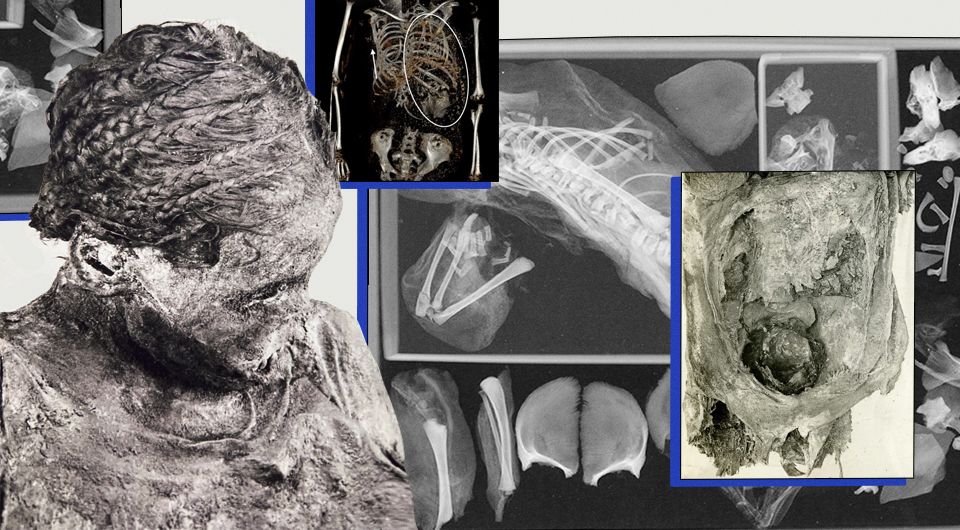

Недавно исследователи углубились в историю молодой египетской девушки, трагически погибшей во время родов в древности. Мумифицированные останки девочки-подростка, которой, как полагают, было от 14 до 17 лет, были проанализированы исследователями, и выяснилось, что к моменту смерти будущая мать рожала близнецов. Но роды приобрели негативный оборот, когда головка первого ребенка застряла в родовых путях, что привело к гибели обоих младенцев и матери.

В 1908 году ее останки обнаружили на кладбище Эль-Багават в египетском оазисе Харга. Ее нашли с остатками плода и плаценты между ногами, что позволяет заключить, что она умерла от акушерских осложнений. Возвращаясь к мумии спустя более столетия, ученые использовали компьютерную томографию (КТ) для дальнейшего исследования, пишет IFLScience.

Позже исследователи заметили, что у младенца, помещенного между ног женщины, не было головы. При ближайшем рассмотрении они поняли, что голова ребенка всё ещё находилась в тазу матери, что заставило их заподозрить, что плод был обезглавлен во время родов — редкое и ужасающее явление, известное как травматическая декапитация плода. Наиболее вероятное объяснение такого ужасающего результата состоит в том, что ребенок родился в тазовом предлежании, то есть вышел ногами вперед. В таких случаях головке ребенка бывает трудно пройти через родовые пути правильно, что приводит к серьезным осложнениям.

«Причиной смерти установлено ущемление головки ребенка в родовых путях из-за тазового предлежания плода во время родов», – подытожили авторы исследования.

Также исследователи подозревают, что бальзамировщики могли не знать, что женщина беременна двойняшками. Для этого не удалили второй плод из тела перед мумификацией. Когда мумия естественно распалась, второй нерожденный ребенок мог переместиться из утробы матери в грудную полость.